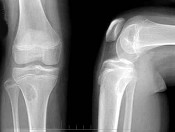

- 单项选择题左膝关节酸胀不适,摄片发现左胫骨上段局限性骨质改变如图示, 最可能的诊断是 ( )

A、非骨化性纤维瘤

B、骨化性纤维瘤

C、内生软骨瘤

D、骨软骨瘤

E、以上均不正确